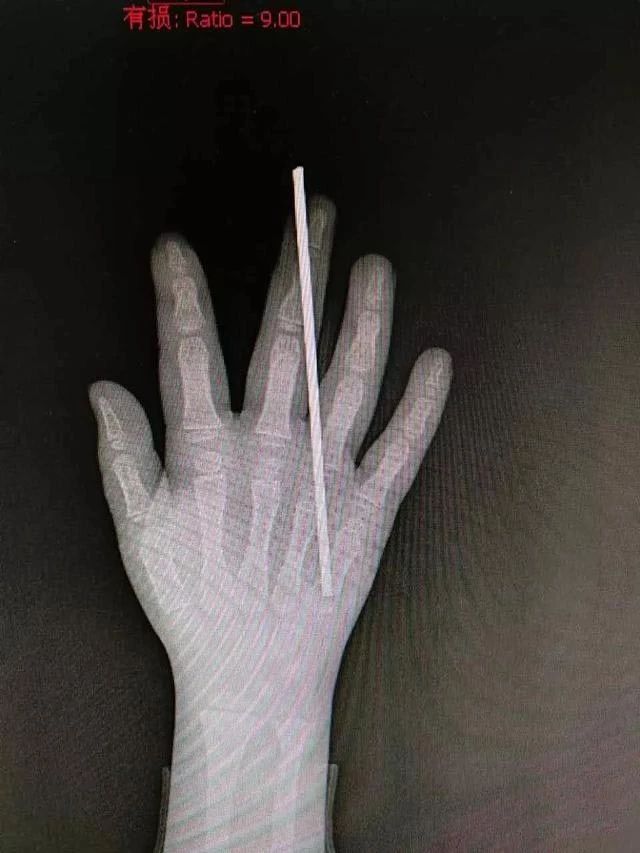

这不去年,一6岁熊孩子墙边玩钢丝

墙上钢丝伸出来大约20多厘米

他不停跳起来手拍钢丝

钢丝越摆动越玩得很开心

就这么拍到正在摆动的钢丝头

右手中指被刺穿

钢丝从中指第二指节斜插

刺穿了指头,医生将钢丝取出后

仔细清理了伤口、探查肌腱

万幸的是肌腱并未受损

参与手术的该院骨科医生介绍

钢丝距离手指两侧的神经、血管束仅几毫米

孩子的手指有惊无险

康复后手指灵活度影响不大